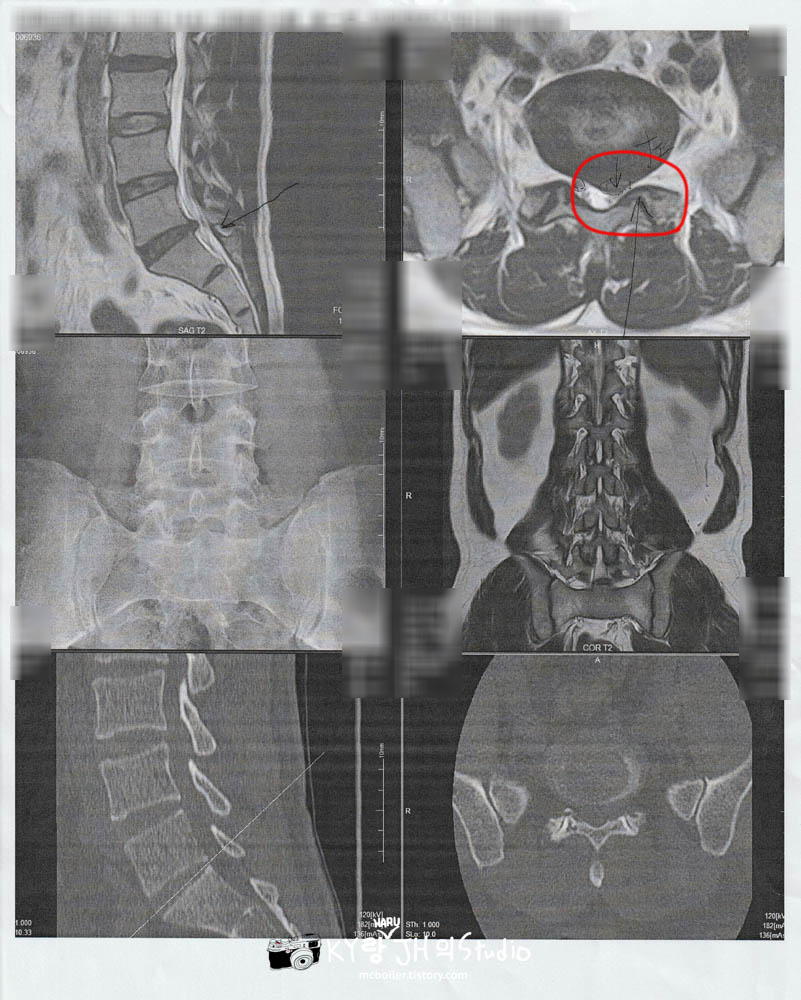

초진(初診)이라 접수하고 이것저것 서류 기입해서 진찰권을 작성하고 잠시 앉아서 대기하다가 진찰실로 들어갔더니 젊은 의사 선생님이셨는데 침대에 누우라더니 골반과 다리를 이리저리 움직이며 아프냐고 물어보시더니 우선 X레이(일본에서는 '렌트겐'이라고 부르는 경우가 많습니다) 랑 MRI 찍고 다시 한번 보자고 하셔서

바로 X레이랑 MRI를 찍고 (MRI 촬영에 20분 정도 걸렸는데 이렇게 오래 걸리는 줄 몰랐습니다)

그렇게 촬영을 마치고 다시 진찰실로 들어갔더니 바로 헤르니아(Hernia : 한국에서는 흔히 '디스크'라고 부르는)라고 진단받고

이 정도면 통증이 꽤 있었을 텐데 아프지 않았냐면서 수술을 권유받았습니다.

수술 전 검사를 위해 9월 29일(목)에 다시 병원을 방문해서 이번에는 CT촬영, 혈액&혈압, 소변 검사, 심전도 검사를 하고

아래 사진진은 수술 후(위)와 수술 전(아래)의 비교 사진으로 신경을 누르고 있던 추간판이 제거된 걸 확인할 수 있습니다